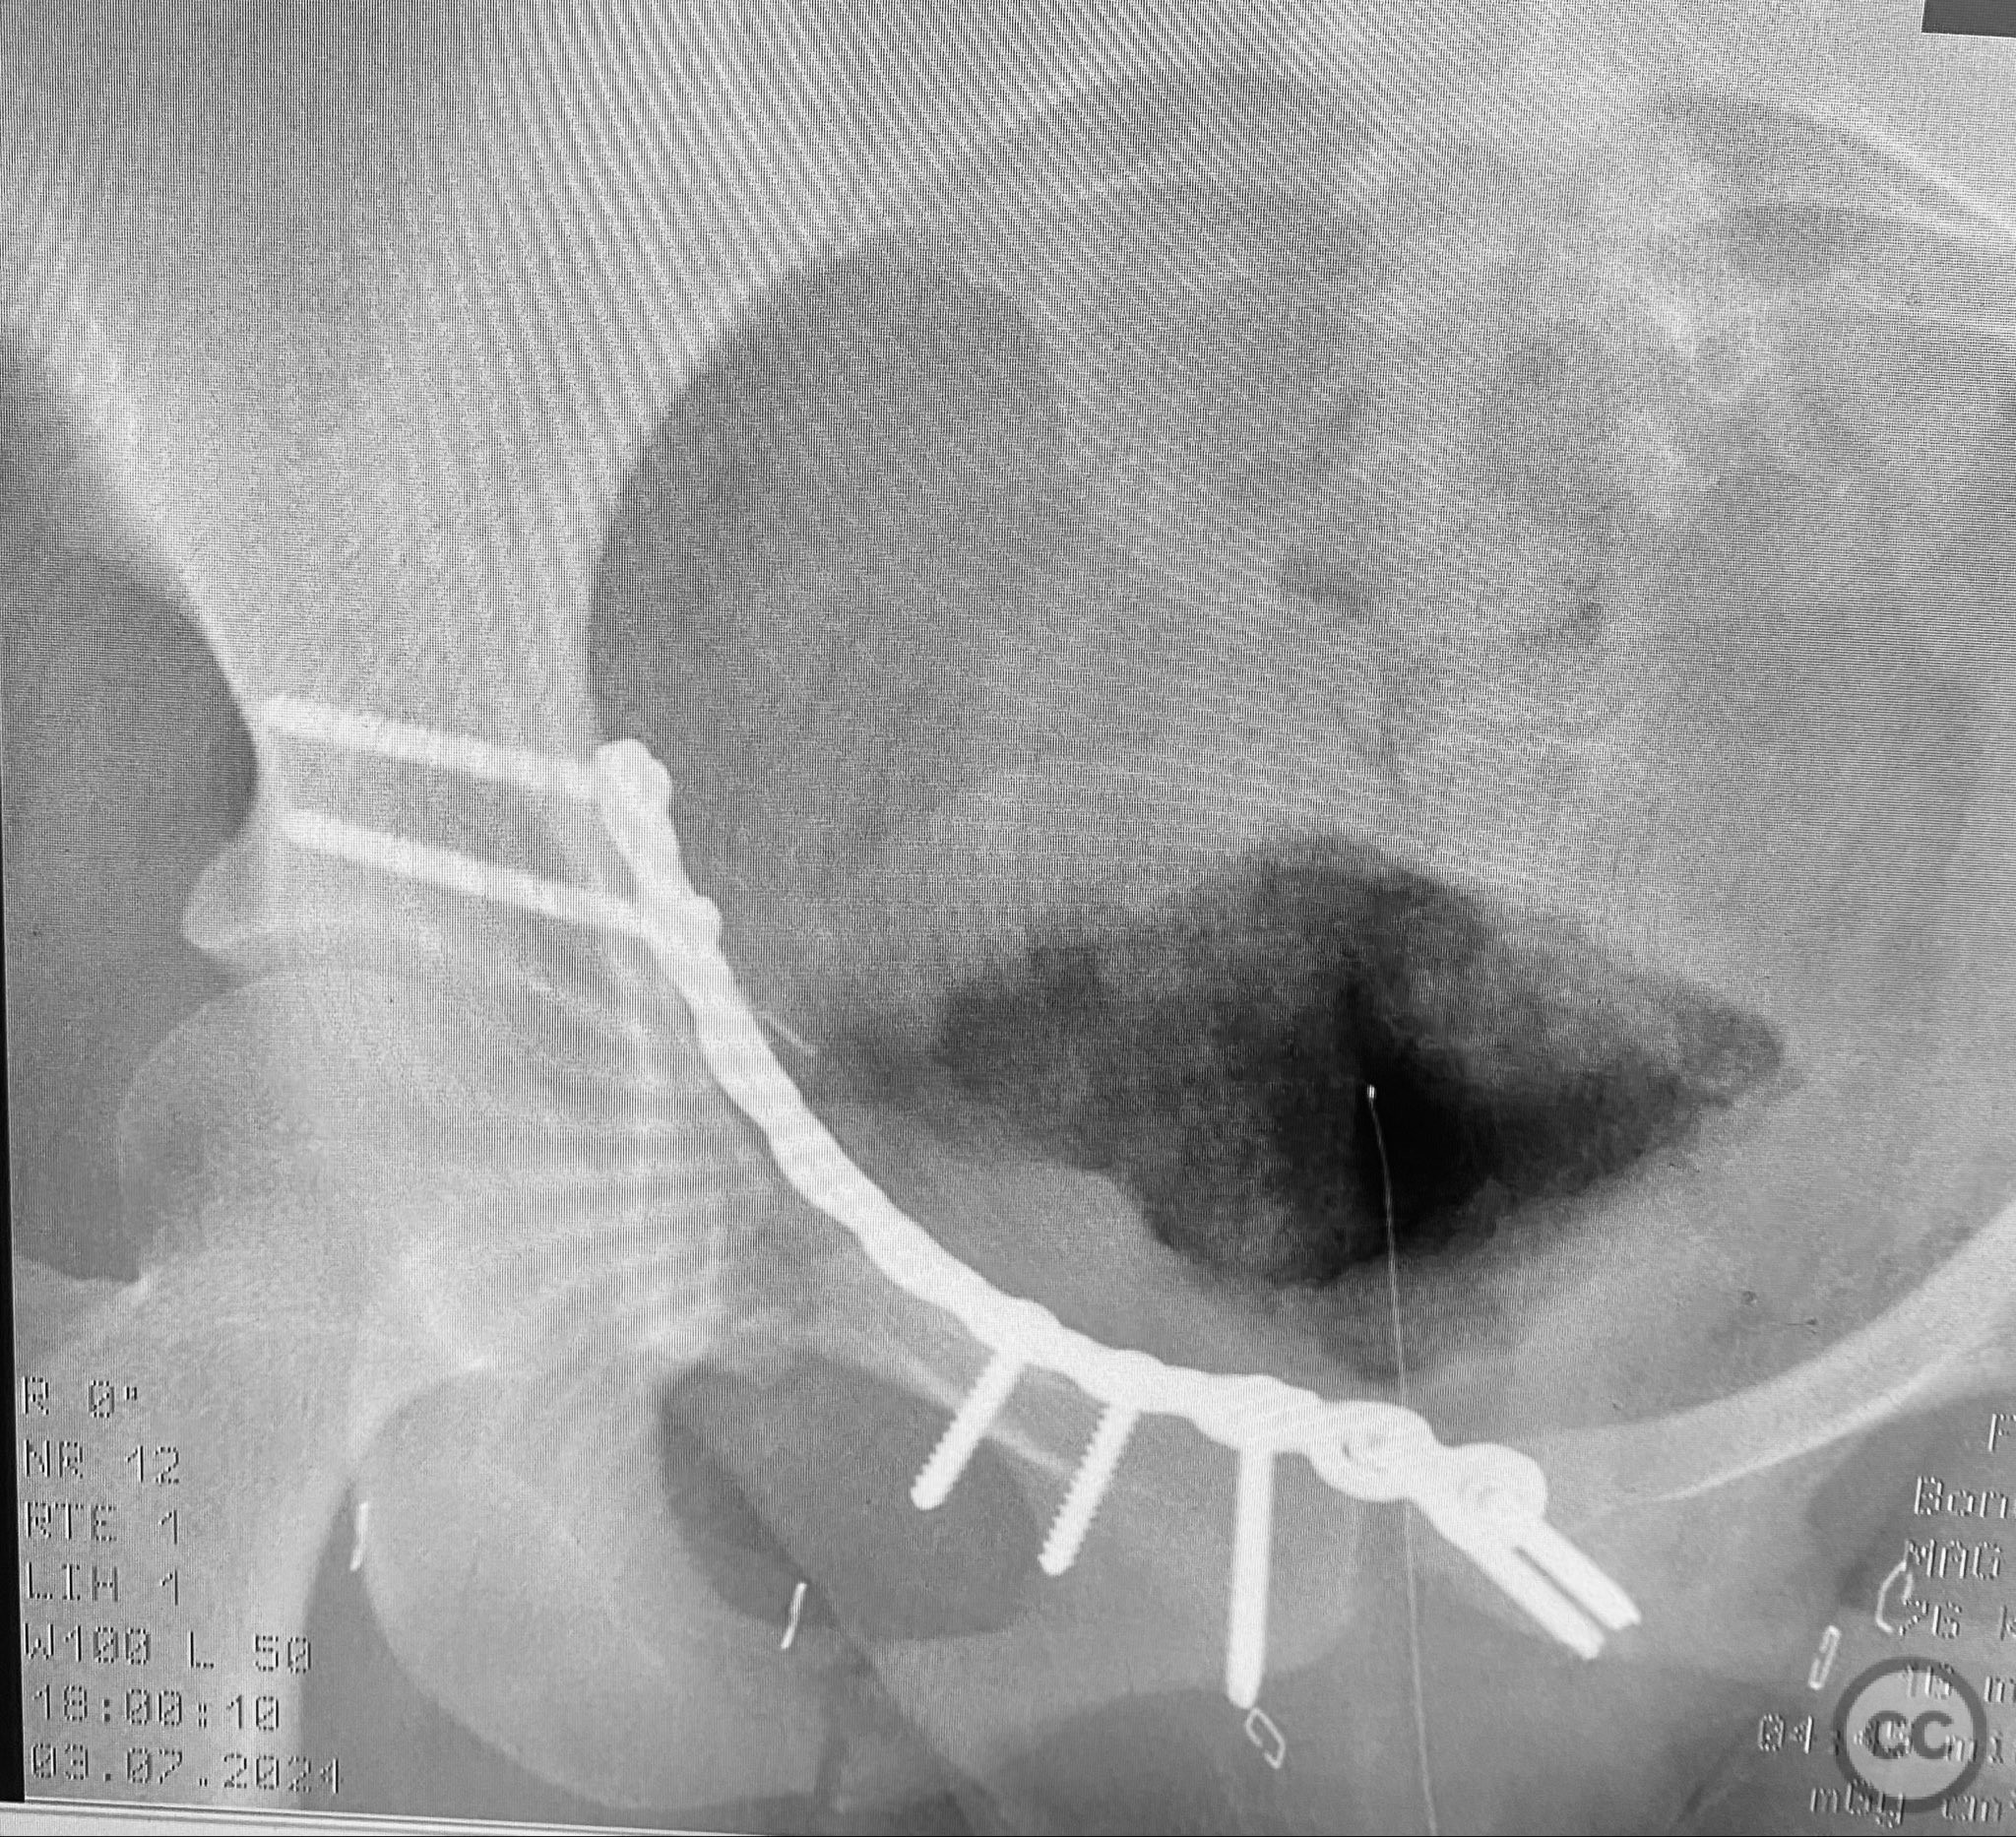

Clinical and radiological findings:  A young adult female sustained a high-energy pelvic injury following a motorcycle crash. She was hemodynamically stable on presentation, with normal neurovascular examination and no evidence of genitourinary, vaginal, or rectal injury. She reported pain localized to both anterior and posterior pelvic regions. Initial plain radiographs (with and without pelvic binder) demonstrated multiple anterior ring fractures and dislocations. The binder images obscured the full extent of injury. Further intraoperative fluoroscopic imaging (AP, inlet, and with lower extremities in "lotus" position) revealed bilateral sacroiliac (SI) joint disruptions (right greater than left), bilateral superior/inferior pubic ramus fractures (right greater than left), and symphyseal diastasis. Notably, the right pubic ramus demonstrated excessive curvature, complicating potential percutaneous screw fixation. AO/OTA classification: 61-C1.3 (bilateral complete disruption of the posterior arch with associated anterior ring injury). Young-Burgess classification: APC III.

Patient positioning:  The patient was positioned supine on a radiolucent operating table under general anesthesia. For intraoperative assessment, the lower extremities were placed in a "lotus" position to enhance visualization of pelvic ring injuries under fluoroscopy.

Intraoperative fluoroscopy with AP and inlet views, as well as dynamic positioning of the lower extremities, was critical in fully delineating the extent of injury, which had been underestimated on preoperative imaging due to binder application. The excessively curved morphology of the right pubic ramus precluded safe or effective straight screw fixation; therefore, ORIF with a contoured plate was performed using intrapelvic exposure for optimal fit and stability. Indirect closed reduction of the SI joints was accepted, followed by percutaneous trans-sacral screw fixation under fluoroscopic guidance. This case highlights the necessity of thorough intraoperative assessment for occult or underestimated injury patterns in complex pelvic trauma, particularly when initial imaging is performed with a pelvic binder in situ.